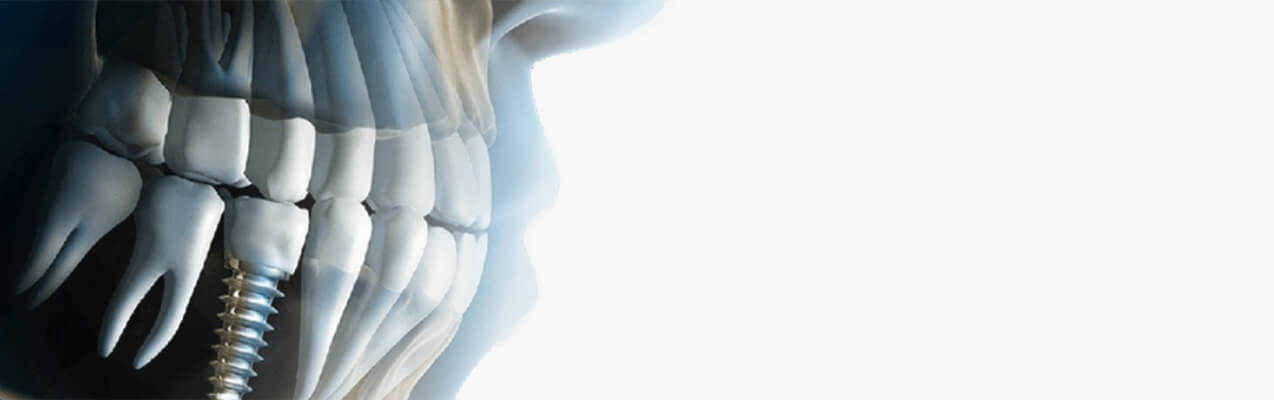

Bu nedenle ağzın mevcut durumunu kontrol etmek ve tanı koymak için ağzınızın röntgenini çekeceğiz, Sonuç olarak, ağız rahatsızlığını tedavi etmek, estetik gülüşler sağlayabilmek için gerekli planları yapmaya yönelik bir adımları atıyoruz. Bir tedavi planı önerirken bile, hasta içeriği tam olarak anlayıp anlayana kadar tedavi uygulanmamaktadır.

Yaptığımız teşhis, ağız sağlığının ve işlevinin bozulmasına katkıda bulunabilecek tüm nedenleri veya riskleri ortadan kaldırmaya yöneliktir.

Tedavi yaklaşımımız, hastaya bütüncül, kişiye özel bakım sağlamayı amaçlamaktadır, bu nedenle teşhisimize sadece diş ve çene bölgesini değil, tüm insan organizmasını dahil ediyoruz.